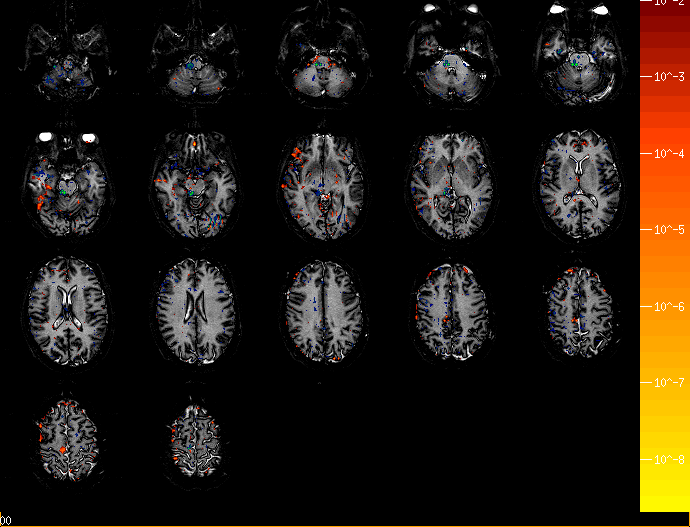

• Nestor's Brain Tracking a Motor Sequence w/o Prior Info ,

various horizontal slices.

• Nestor's Brain Tracking a Motor Sequence with Prior Info ,